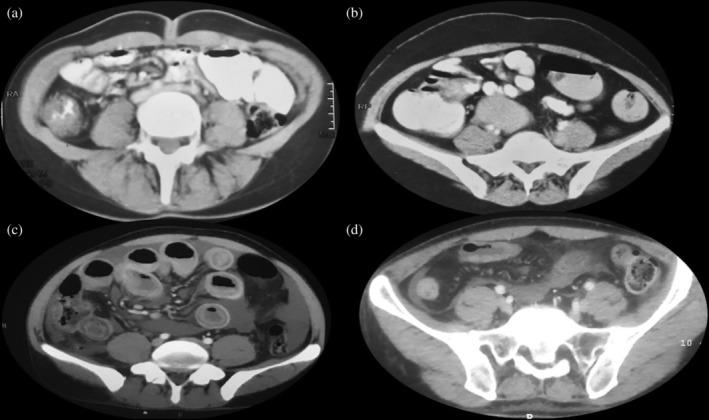

回盲部增厚:常见问题的临床处理方法

Ileocecal thickening: Clinical approach to a common problem.

Ileocecal thickening (ICT) is a common finding on radiological imaging. It can be caused by a variety of inflammatory, infectious, or neoplastic conditions, and evaluating a patient of ICT can be a challenging task. Intestinal tuberculosis (ITB), Crohn's disease (CD), and adenocarcinoma are the most common causes. Enteric bacterial infections, cytomegalovirus, histoplasmosis, amebiasis, systemic vasculitis, lymphoma, etc. should be suspected in appropriate clinical settings. However, it could often be a spurious or nonspecific finding. A thickness of more than 3 mm in a normally distended small bowel is usually considered abnormal. Detailed evaluation of imaging of the site and extent of thickening; the degree and pattern of thickening; and the associated findings, such as degree of fat stranding, fibrofatty proliferation, adjacent lymph nodes, and solid organ involvement, should be performed. Ileocolonoscopy is an important tool for diagnosing and obtaining samples for tissue diagnosis. Histopathology is usually the gold standard for diagnosis, although-not uncommonly-findings could be nonspecific, and reaching a definitive diagnosis is difficult. As such, a systematic approach with the integration of clinical, biochemical, radiological, endoscopic, histological, and other laboratory tests is the key to reaching a diagnosis. In this article, we review the causes of ICT and present a clinical approach for the management of ICT.

回盲部增厚(ICT)是放射影像学上的常见表现。它可由多种炎症、感染或肿瘤性疾病引起,评估ICT患者可能是一项具有挑战性的任务。肠结核(ITB)、克罗恩病(CD)和腺癌是最常见的病因。在适当的临床情况下,应怀疑肠道细菌感染、巨细胞病毒、组织胞浆菌病、阿米巴病、系统性血管炎、淋巴瘤等。然而,它往往可能是一种假阳性或非特异性表现。正常扩张的小肠厚度超过3mm通常被认为是异常的。应详细评估增厚部位和范围的影像学表现、增厚程度和方式,以及相关表现,如脂肪浸润程度、纤维脂肪增生、相邻淋巴结和实体器官受累情况。回结肠镜检查是诊断和获取组织诊断样本的重要工具。组织病理学通常是诊断的金标准,尽管结果往往可能是非特异性的,难以做出明确诊断。因此,综合临床、生化、放射、内镜、组织学和其他实验室检查的系统方法是做出诊断的关键。在本文中,我们回顾了ICT的病因,并提出了ICT的临床管理方法。